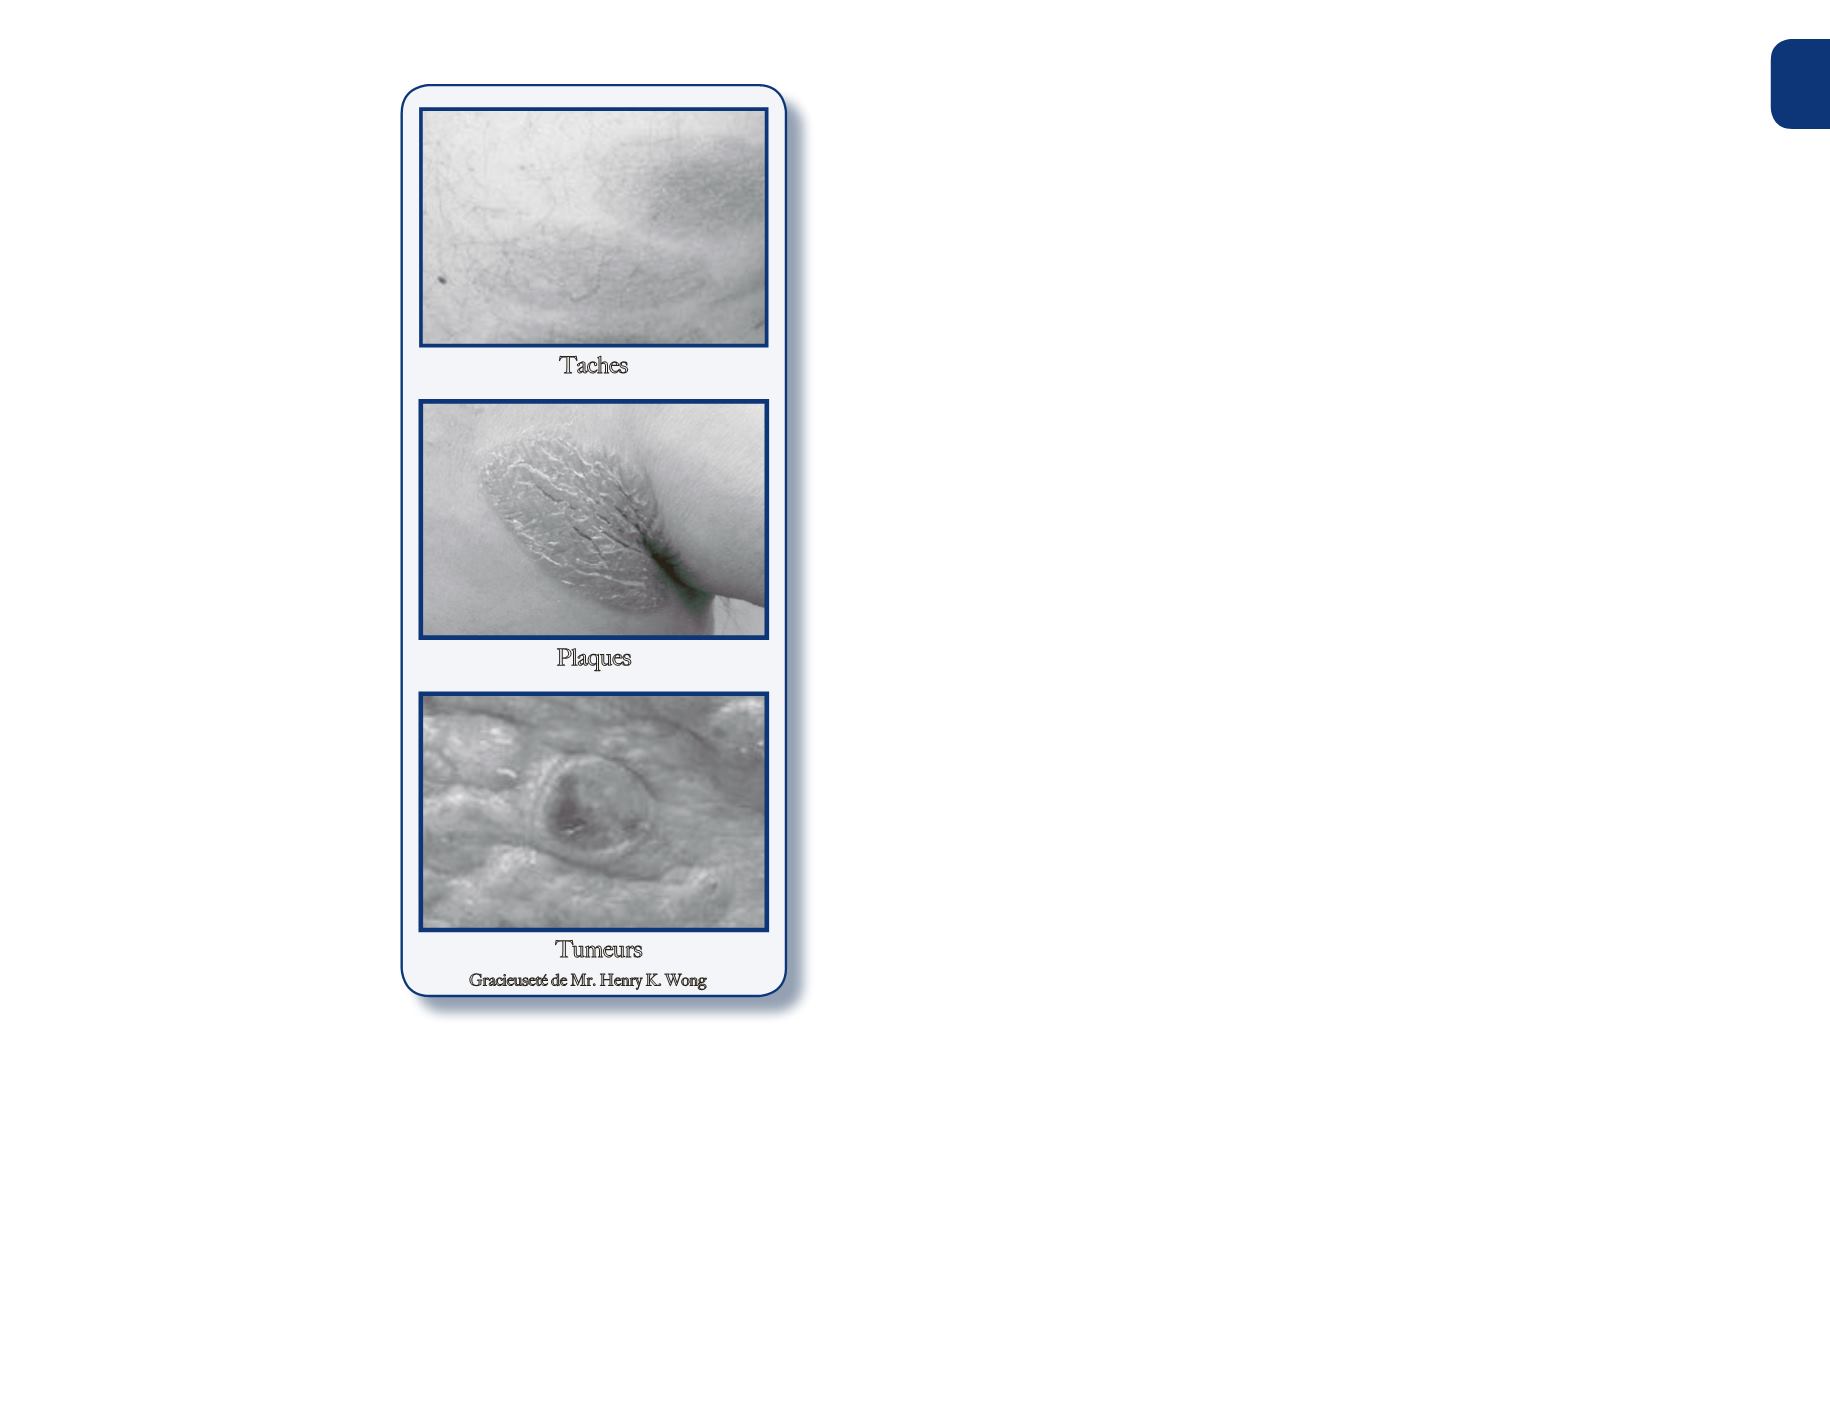

ces « lésions » de la peau. Les

taches sont planes, souvent

squameuses et ressemblent à

une « éruption ». Les plaques

représentent des lésions plus

épaisses et surélevées. Les

plaques et les taches deMF

sont souvent confondues avec

l'eczéma, le psoriasis ou la

dermatite « non spécifique »

jusqu'à ce qu'un diagnostic

exact soit posé.

Les tumeurs sont des « bosses

» ou « nodules » surélevés,

qui peuvent s'ulcérer (plaies

ouvertes). Une caractéristique

commune est la démangeaison,

bien que certains patients

n’éprouvent pas ce symptôme.

Une grandemajorité des

patients se présentent avec

des taches ou des plaques, les

tumeurs sontmoins fréquentes.

Il est possible d'avoir tous les

trois types de lésions enmême

temps,mais c’est plutôt rare.

Tumeurs

Plaques

Taches

GracieusetédeMr.HenryK.Wong